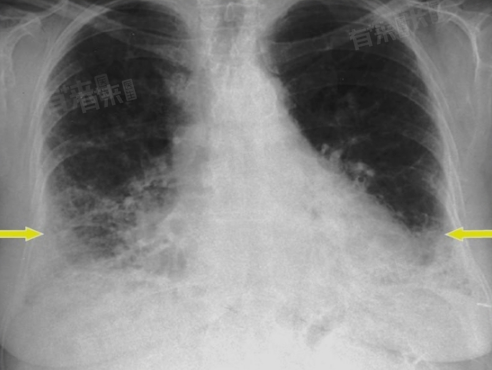

- 广泛分布:若肺纤维灶广泛分布于肺部,特别是涉及多个肺叶或肺段,可能对肺功能造成较大影响。这种广泛的肺纤维化可能导致肺功能下降、呼吸困难加重等症状,甚至影响患者的生存质量,需要积极治疗以延缓病情进展。